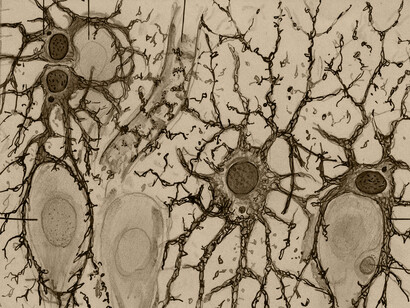

En 1887, Cajal obtiene por traslado la cátedra en Barcelona. Allí se dedica a consolidar su obra sobre el sistema nervioso, basándose en dos elementos con los cuales ha venido trabajando: el trabajo sobre el embrión en vez del adulto y el mejoramiento que ha realizado del método tintorial de Golgi, «el de la doble impregnación». Y así surge resplandeciente en su microscopio, la unidad fundamental del sistema nervioso: «la célula que Waldeyer bautizará con el nombre de neurona» (Pollack, K.).

Las neuronas son células de formas delicadas y elegantes, las misteriosas mariposas del alma, cuyo batir de alas quién sabe si esclarecerá algún día el secreto de la vida mental.